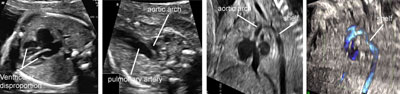

Interrupted aortic arch

Legend:Interrupted aortic arch: there is ventricular disproportion and the ascending aorta is not connected to the descending portion

Coarctation/tubular hypoplasia of aortic arch

Legend:Coarctation/tubular hypoplasia of aortic arch: ventricular disproportion with dominance of the right cavities, small aortic arch compared to the ductal arch in the transverse view, small and tortuous aortic with the impression of a shelf in the longitudinal views